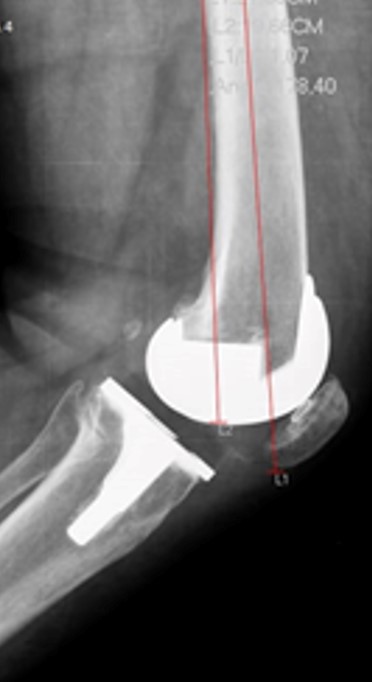

Foram analisadas as imagens de radiografias do joelho operado obtidas no pós-operatório imediato em ântero-posterior (AP) e perfil, bem como as imagens em AP e perfil do joelho com carga, realizadas com 3 meses de seguimento clínico, conforme protocolo da instituição. Os exames de imagem foram avaliados por um único observador membro do grupo de cirurgia do joelho. A análise radiográfica foi realizada de forma cega sem identificação do paciente. O software utilizado para o estudo foi o mDicomViewer 3.0 (Microdata, RJ-Brasil, 2007). O alinhamento coronal e sagital foram determinados pela medição de cinco ângulos radiográficos.15 O primeiro foi avaliado na radiografia em AP. Essa análise foi feita através de um ângulo formado pela superfície distal do componente femoral e o eixo da diáfise do fémur, além de um segundo ângulo formado entre o planalto tibial e o eixo da diáfise da tíbia (figura 2 A-B). Além disso, analisamos o ângulo tibio-femoral formado entre os eixos anatómicos do fémur e da tíbia (figura 3). A avaliação do alinhamento no plano sagital foi realizada através da radiografia em perfil, determinando-se o ângulo entre a parte mais distal da superfície de fixação femoral e o eixo da diáfise do fêmur (figura 4). De forma similar, a avaliação do alinhamento da tíbia nessa incidência corresponde ao ângulo entre o planalto tibial e o eixo da diáfise da tíbia (figura 5). O alinhamento patelofemoral não foi avaliado.

Figura 4: Ângulo entre a parte mais distal da superfície de fixação femoral e o eixo da diáfise do fêmur.